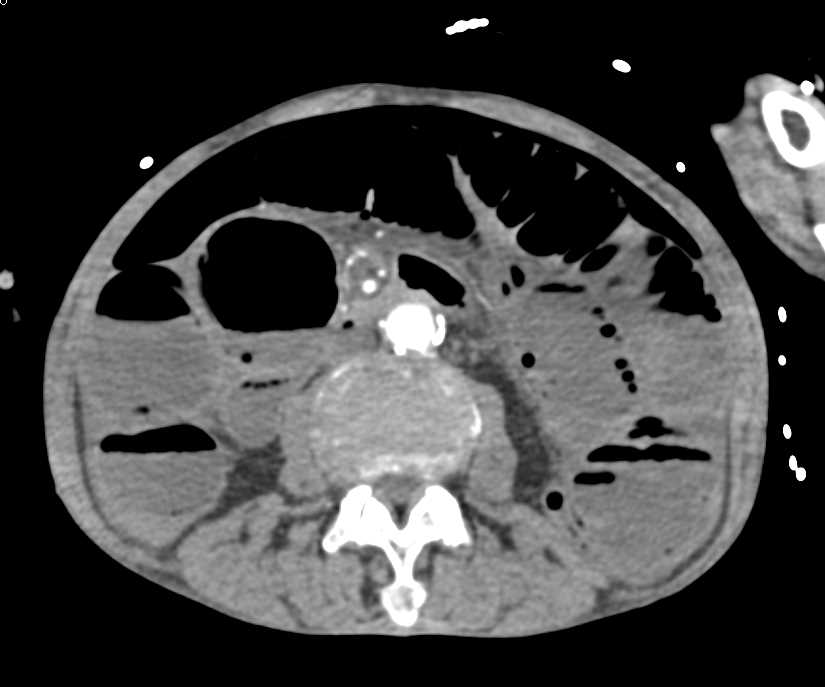

Carcinoma Hepatic Flexure Obstructs the Bowel